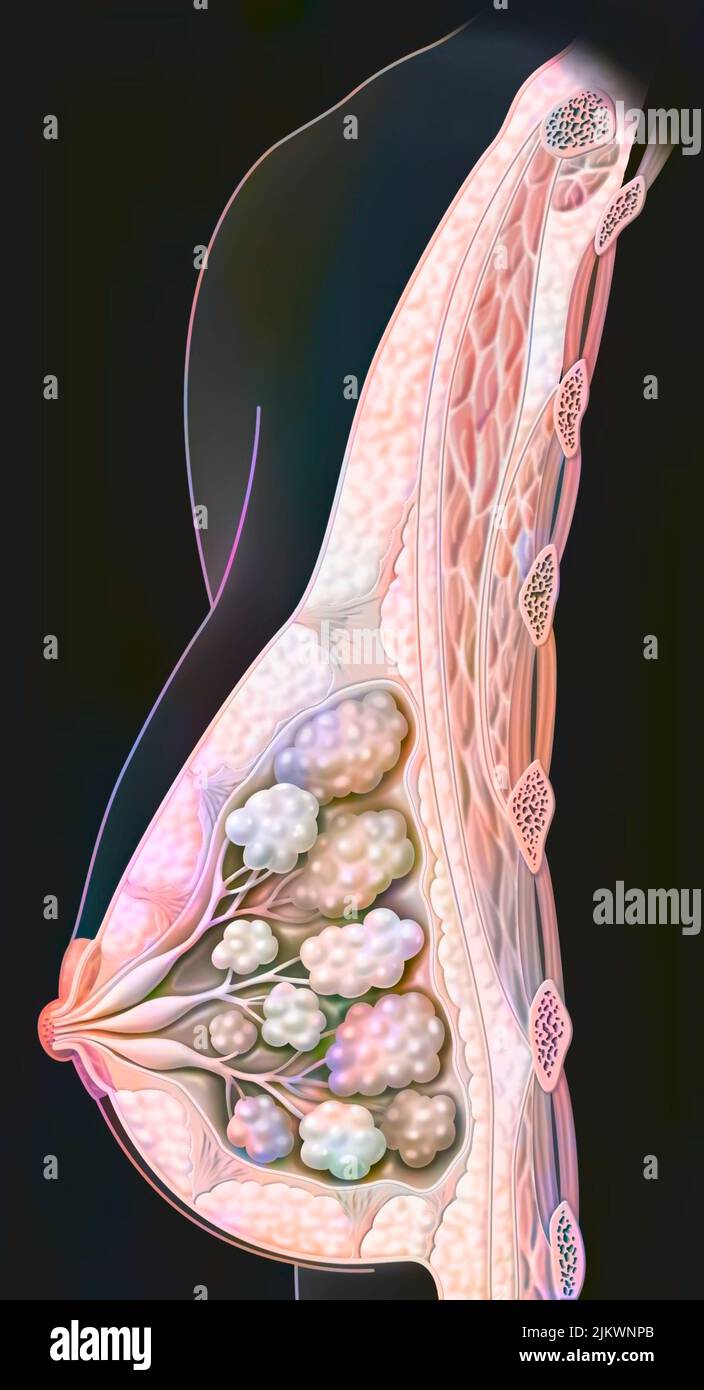

RF2JKWPFD–Auto-échantillonnage vaginal : l'écouvillon humide est administré au médecin pour analyse.